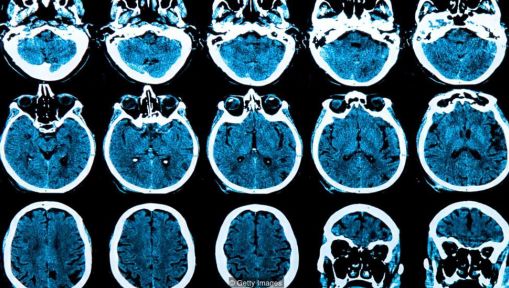

全世界的医生都在越来越多的使用AI软件来检测癌症或眼部疾病的早期症状,但是最新研究成果表明,人工智能还能在一个人出现任何病兆之前的好几年,就预测到他是否会患上像阿尔茨海默病这样的疾病。